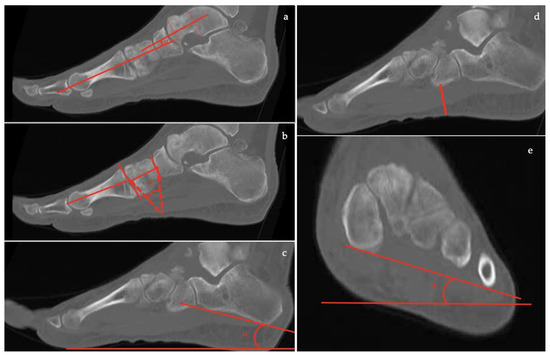

- Talar–first metatarsal angle (Meary’s angle), the normal value is 0 ± 10 degrees and is increased in flatfoot deformity (often >20°, apex directed plantarly) (Figure 5);

- Calcaneal pitch, the angle between the line parallel to the ground and the line along the inferior inclination axis of the calcaneus (normal, 20–30°; flatfoot, <20°) (Figure 6);

- Talocalcaneal angle is formed by the long axis of the rearfoot and the midtalar line. This angle is increased in pronated feet on both the AP and lateral views (normal <45°, flatfoot >45°) (Figure 7);

- Calcaneal-fifth metatarsal angle, defined as the angle formed between the tangent to the inferior aspect of the calcaneus and a line drawn along the inferior aspect of the base and head of the fifth metatarsal (normal <170°, flatfoot >170°) (Figure 8).